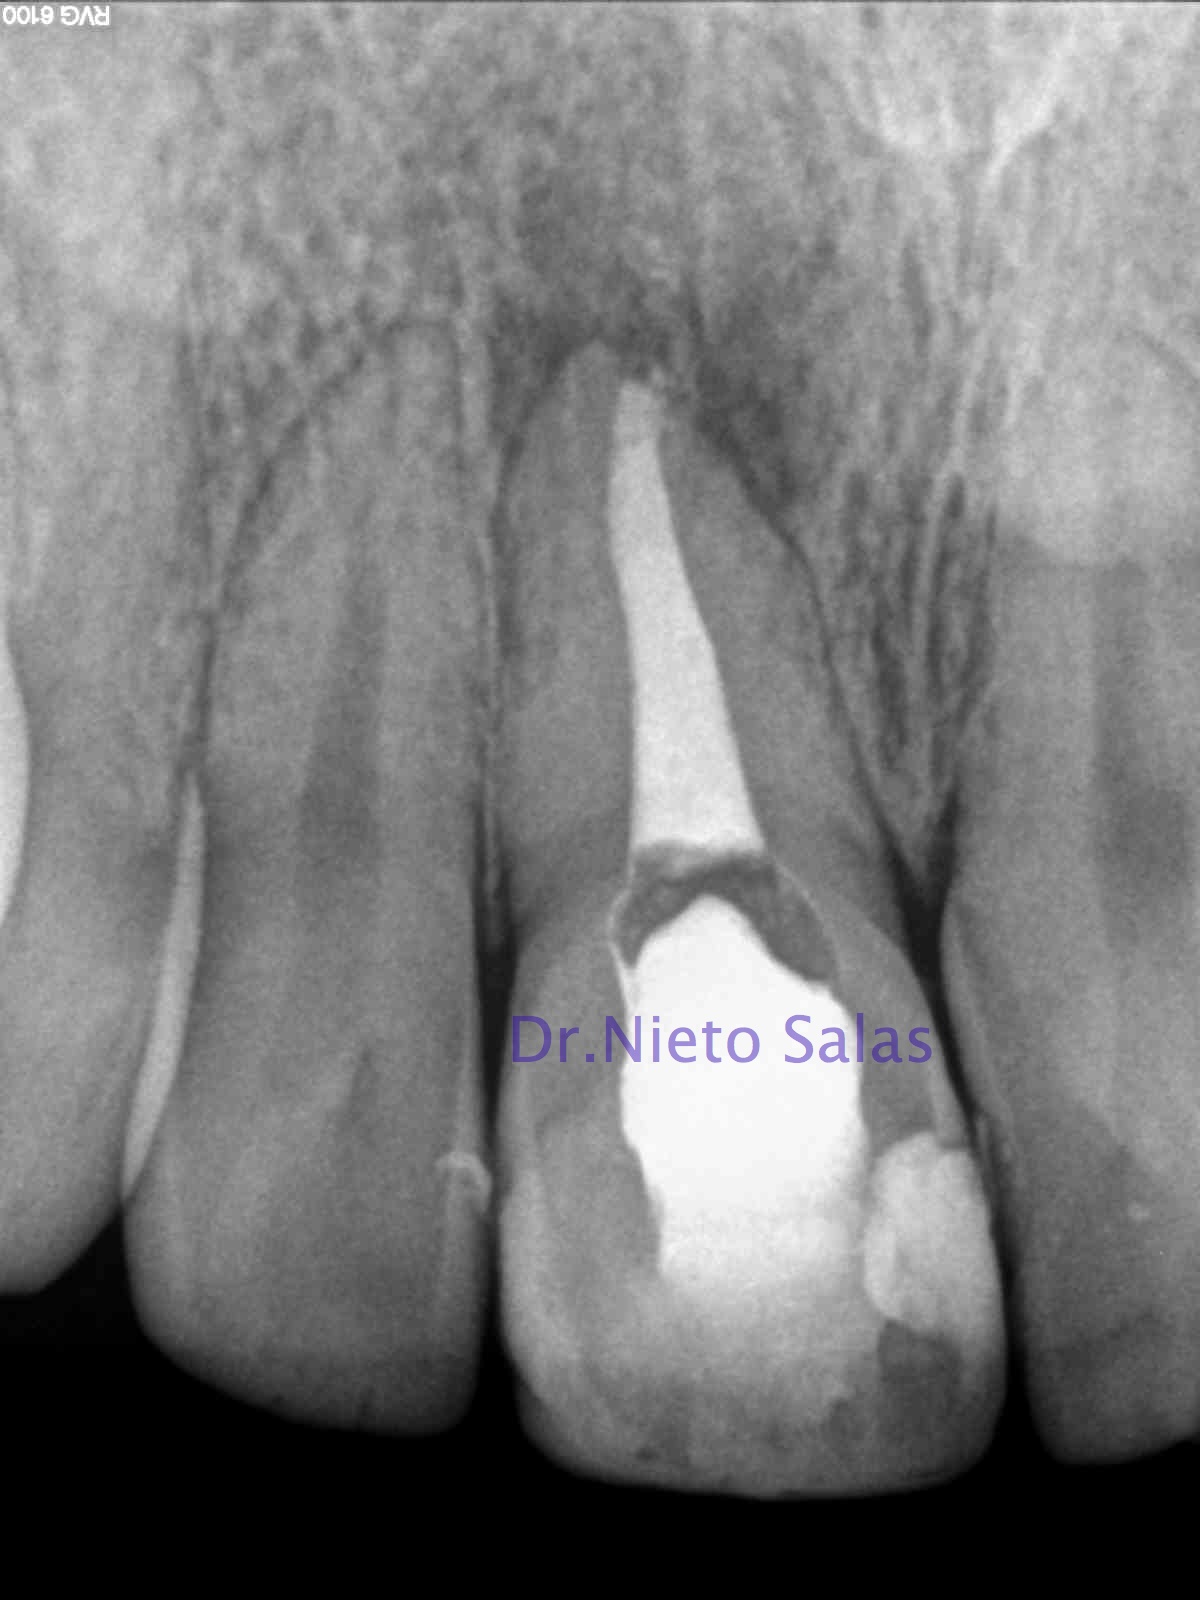

CASO 1:

El primer caso, se trata de una pieza que nos mandan, un 1.2, con una apertura, para ver que podemos hacer:

Como podemos apreciar, se trata de una pieza con una reabsorción externa en el tercio apical e incluso del mismo ápice, y en el cuello se observa un defecto. Desde un primer momento, se le explica al paciente que el pronóstico del mismo es dudoso y que puede que necesite complementar el tratamiento con una microcirugía apical.

Le planteamos el tratamiento con un sellado apical con M.T.A. por si necesitásemos hacer la cirugía endodóntica, y posterior sellado con gutapercha termoplástica.

Decidimos colocar un medicamento intraconducto durante unos 15-20 días. Nuestro medicamento de elección será el Hidróxido de Calcio, sabemos que tiene una influencia sobre los osteoclastos , reduciendo su actividad, y estimulando la reparación (Tronstad 1981). El uso del M.T.A. también tiene un componente de acción muy similar al Ca(OH)2, con lo que también nos ayudará.

Como hemos comentado anteriormente, crearemos una barrera apical con M.T.A., asegurandonos el sellado del mismo. Y finalmente sellaremos con gutapercha termoplástica con la Pistola Obtura II.

Llamamos al paciente a revisión al año:

Vemos una regeneración de la lesión, con lo que va evolucionando positivamente. El defecto en el cuello del diente, sigue presente, se planificó el caso para realizarlo en el momento de la cirugía, pues pensábamos que al final necesitaríamos complementar el tratamiento, pero ahora solo vamos a vigilar la pieza.